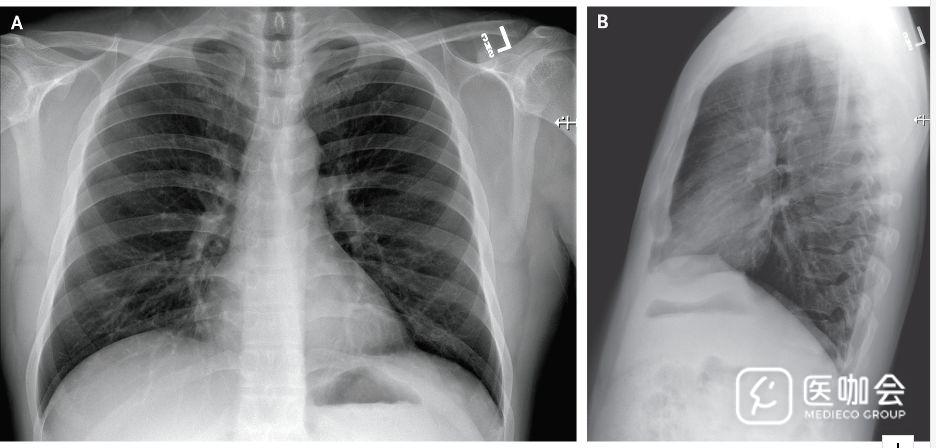

除了有高甘油三酯血症病史外,患者身体健康,且不吸烟。体格检查显示患者体温37.2°C,血压134/87mmHg,脉搏110次/分,呼吸频率16次/分,氧饱和度96%。肺部听诊显示干啰音,胸片无异常(图1)。

图1. 患者胸片